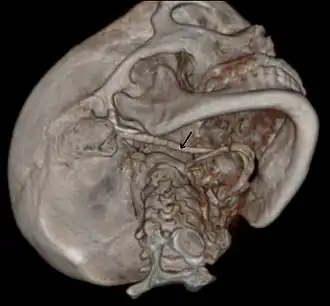

3D-reconstructed CT scan showing bilateral stylohyoid ligament ossification -

3D reconstructed CT scan showing elongated styloid process (right side)

Imaging is important and is diagnostic. Visualizing the styloid process on a CT scan with 3D reconstruction is the suggested imaging technique.[13] The enlarged styloid may be visible on an orthopantogram or a lateral soft tissue X ray of the neck.